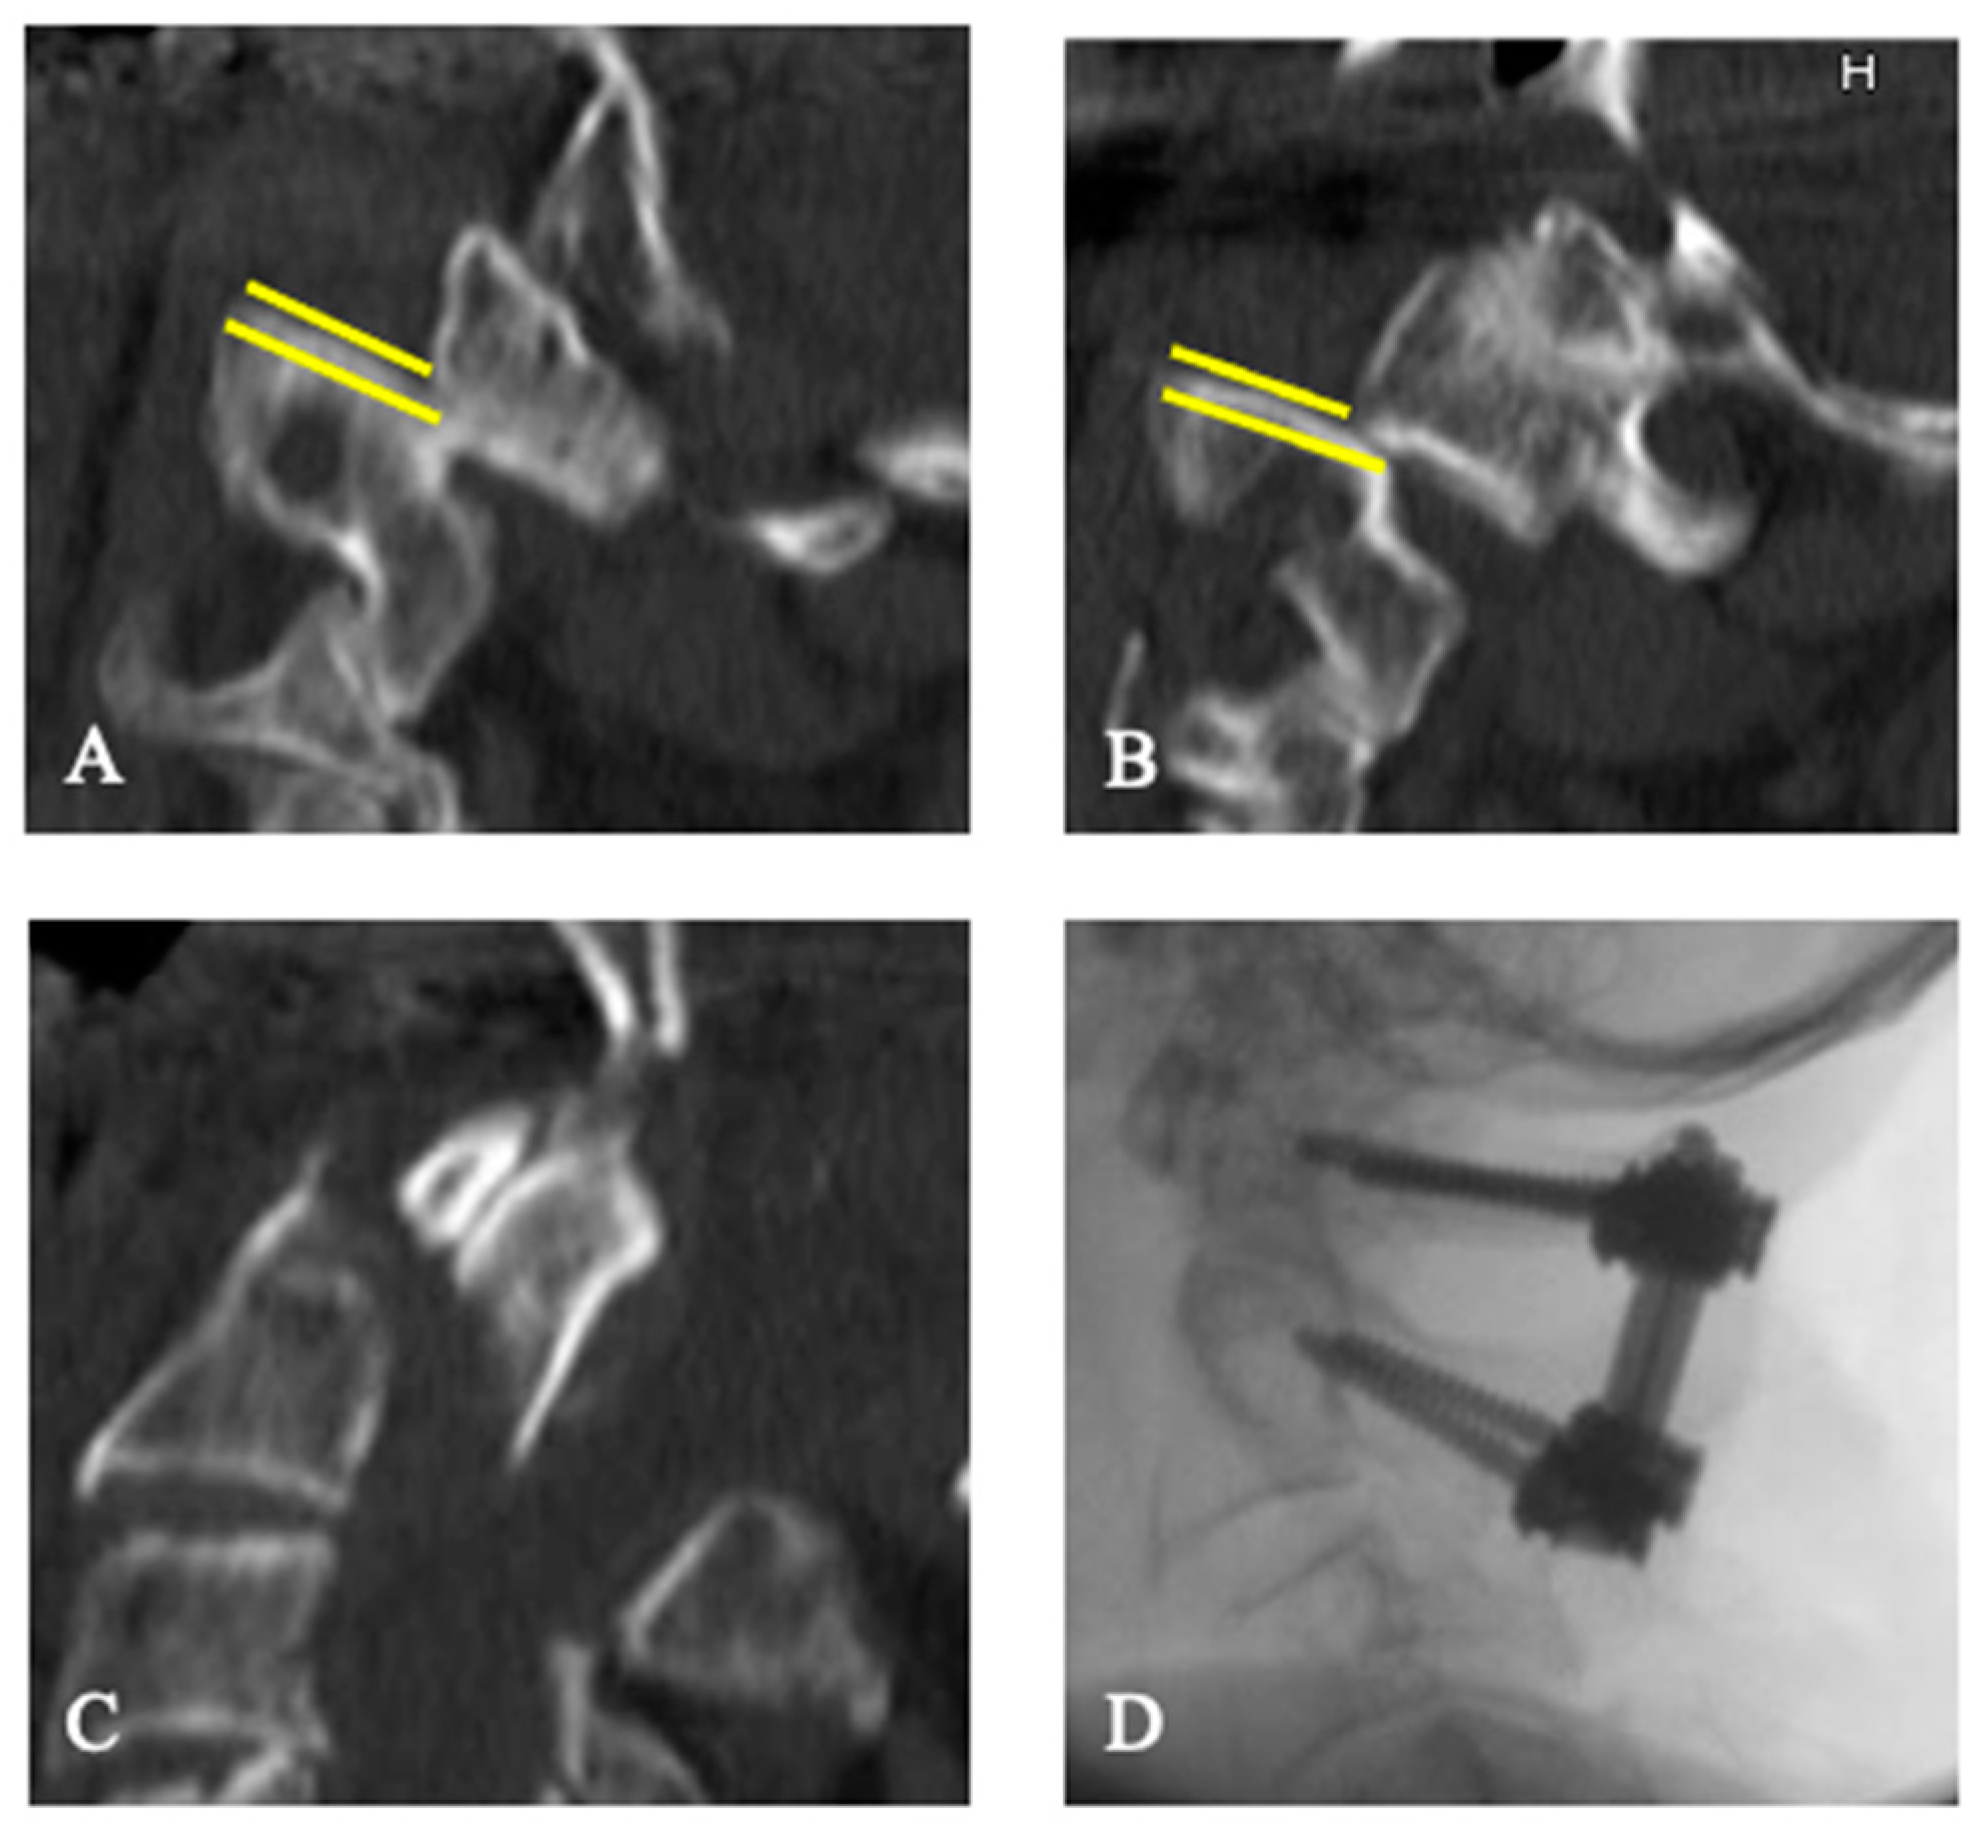

3.2. Treatment